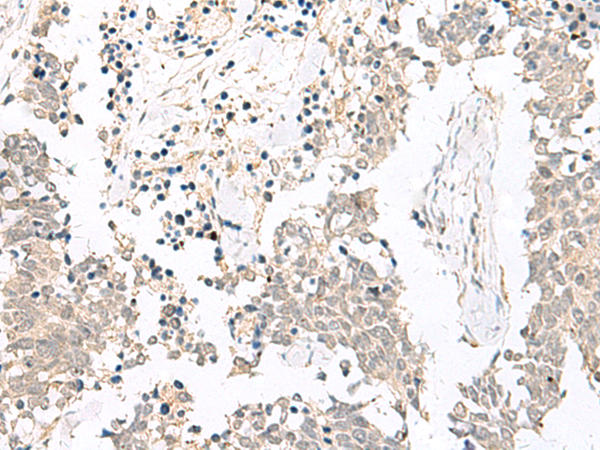

ELISA, IHC |

IHC positive control: |

Human lung cancer and Human esophagus cancer |

IHC Recommend dilution: |

20-100 |